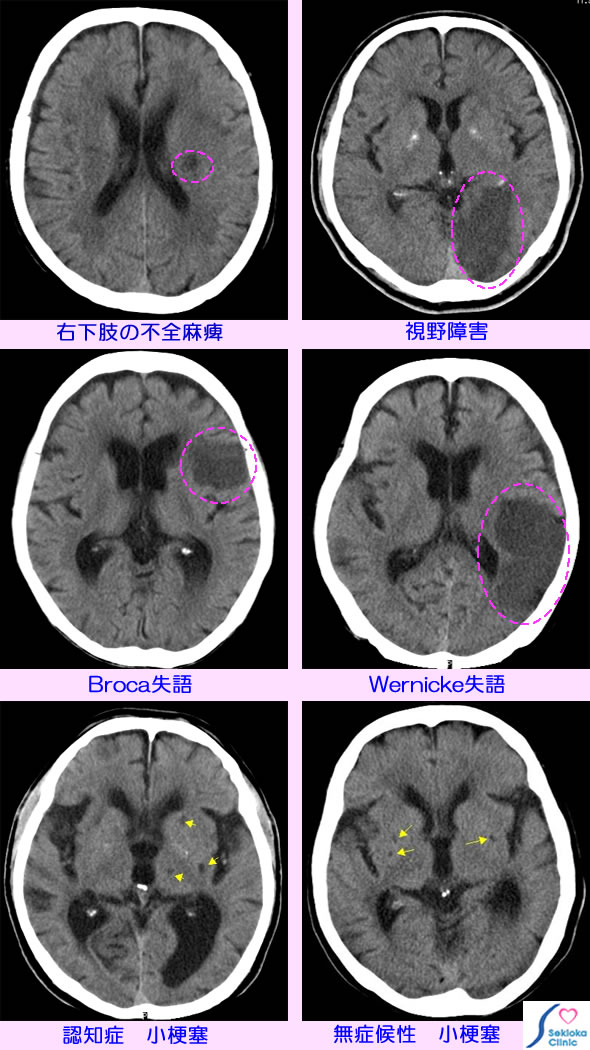

| 症状 | 脳梗塞の部位、大きさにより症状は異なります。添付画像は異なる部位の梗塞と症状を掲載しました。上段左は右下肢の歩行障害、脱力で来院、外来通院治療で軽快。上段左は四肢の運動障害はないが、視野障害で受診、眼科も受診されていた。中段左は 発語障害(Broca失語)、中段右は会話を理解できない(Wernicke失語)、四肢の運動障害はありません。下段左は軽度認知症で検査、脳質拡大と多数の小梗塞(黄矢印)を認めます。下段左は運動障害等はありません(無症候性)が多数の小梗塞を認めます。 |